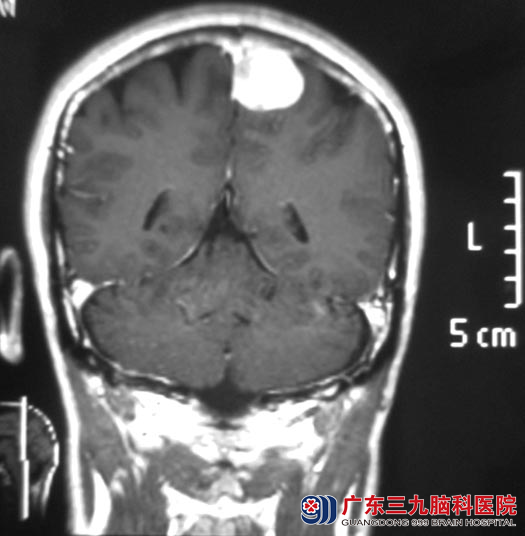

一周前去医院体检,头颅CT提示左侧顶部大脑镰窦旁占位,考虑脑膜瘤可能性大;广东三九脑科医院头颅MR提示:左侧顶部镰窦旁占位,大小约3.0cm×3.0cm×2.5cm。

10月19日,综合神经外科 鲁明主任主刀,在全麻下行左侧顶部镰窦旁占位切除术,术中显微镜下见靠近大脑镰处红色肿瘤组织,表面回流静脉丰富,分离肿瘤边缘,肿瘤边界清楚,沿大脑镰向下分离肿瘤基底部,粘连紧密,硬膜供血,血供丰富,肿瘤质软,完整分离切除肿瘤,手术顺利。现杨先生已康复出院。术后病理结果为:脑膜皮细胞型脑膜瘤(WHO I级)。